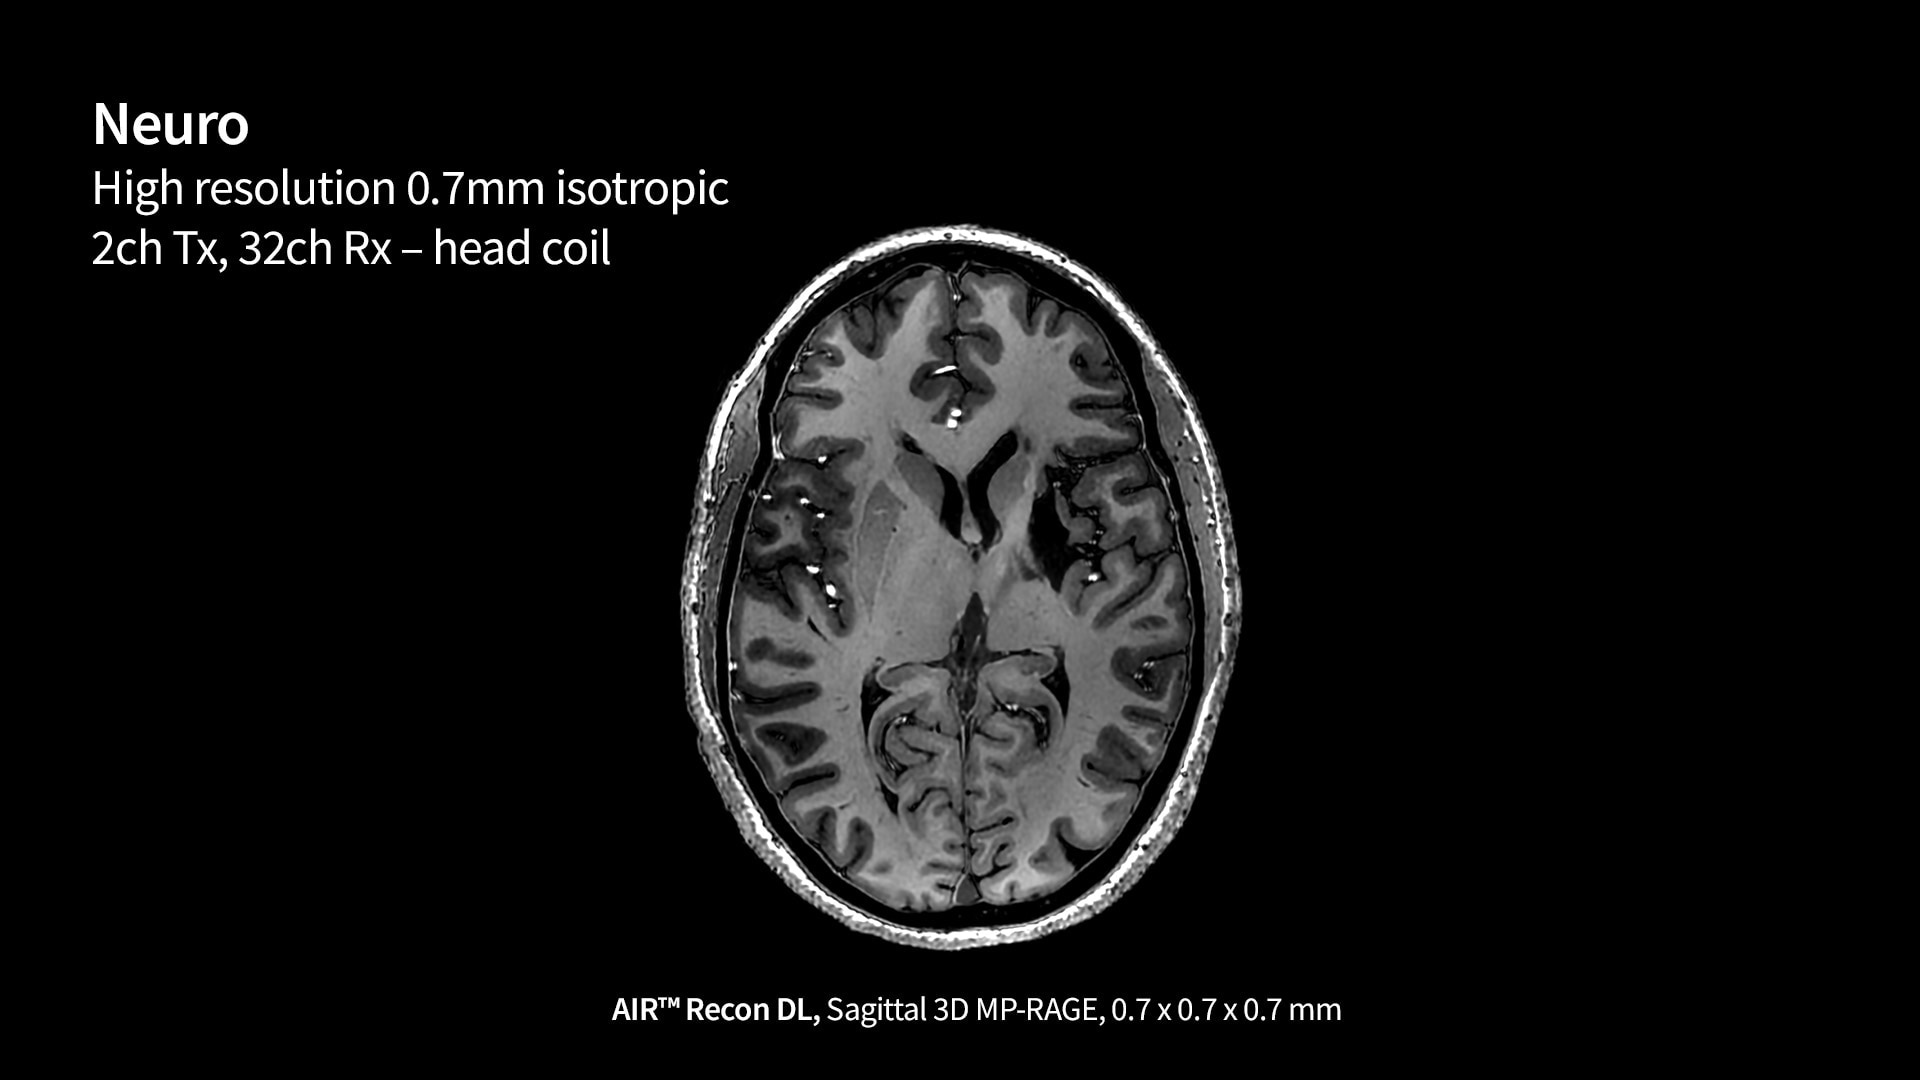

SIGNA 7T powered by a common suite of SIGNA Imaging Applications

Users have access to our latest state-of-the-art applications along with deep-learning tools like AIR x™ Brain and Knee as well as AIR™ Recon DL, while delivering the diagnostic confidence of an ultra-high-field system.